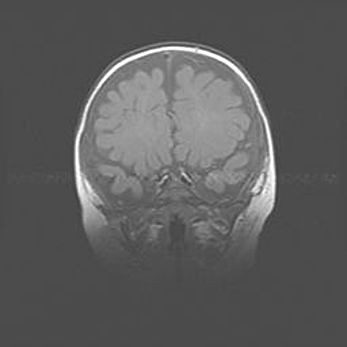

Наружная гидроцефалия с возможной атрофией височных областей.

Возраст: 28 дней

Вес: 3670 г

Пол: мужской

Окружность головы: 38 см

Срок гестации: 40 недель

Гидроцефалия головного мозга у новорожденных – это заболевание, которое характеризуется скоплением избыточного количества спинномозговой жидкости в желудочковой системе головного мозга в результате затруднения её перемещения от места выработки к месту поглощения в кровеносную систему или вследствие нарушения абсорбции. При открытой наружной форме гидроцефалии у новорожденных расширяются и переполняются субарахноидные пространства.

При нормотензивных  формах,  которые,  как  правило,  являются  следствием  перенесенных ишемических  повреждений  паренхимы  мозга,  возможно  сочетание микроцефалии  с нормотензивной гидроцефалией. В основе данных изменений лежит атрофия больших полушарий с преимущественной  локализацией  в  лобно-височных  областях.